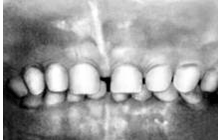

Рис. 9. Системная гипоплазия (выраженная стадия поражения постоянных резцов, клыков и первого моляра).

Рис 10. Гипополазия центральных резцов верхней челюсти с поражением их вестибулярной и небной поверхностей.